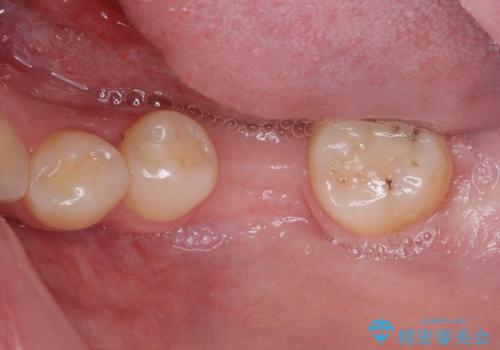

虫歯と抜いたままの奥歯とデコボコの前歯 総合歯科治療

- 放置した虫歯や抜いたままの奥歯、前歯のデコボコを気にして来院された患者様です。

口元の突出感は少なく、下顎の叢生は軽微なものであったので、叢生の強い上顎左右の小臼歯を1本ずつ抜歯し、ワイヤー装置にて矯正治療を行うこととしました。

矯正治療を行う前に、根管治療の必要な上顎前歯と下顎大臼歯の根管治療を行い、矯正治療の途中で下顎の欠損部にインプラント埋入することとし、矯正治療後に補綴治療を行うこととしました。